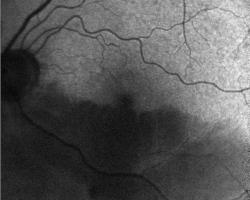

- OG : OBACR inférieure avec œdème rétinien inférieur qui épargne la fovéa sur sa partie supérieure. Rétrecissement du calibre artériel des vaisseaux inférieurs

- Images en autofluorescence et infrarouge du FO OG : perte la fluorescence et du reflet normal de la partie inférieure de la rétine

FO : cf. images jointes